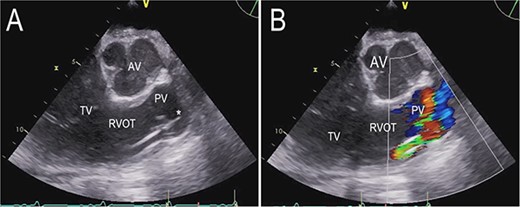

Re-sternotomy was performed. The pulmonary trunk (PT) was clamped. A 10-mm prosthetic polyester graft was anastomosed to the PT. After subxiphoid tunneling of the graft the transjugular outflow cannula was replaced by a cannula in the anastomosed graft. The cannula in the right FV remained in position in the right atrium (Figs 3 and 4). The hemodynamic situation with LVAD and RVAD flow improved immediately.

Anteroposterior thoracic radiography after LVAD implantation (A). Anteroposterior thoracic radiography after RVAD cannulation of the PT (B). Tip of cannula in the right FV, tip of cannula in the PT.